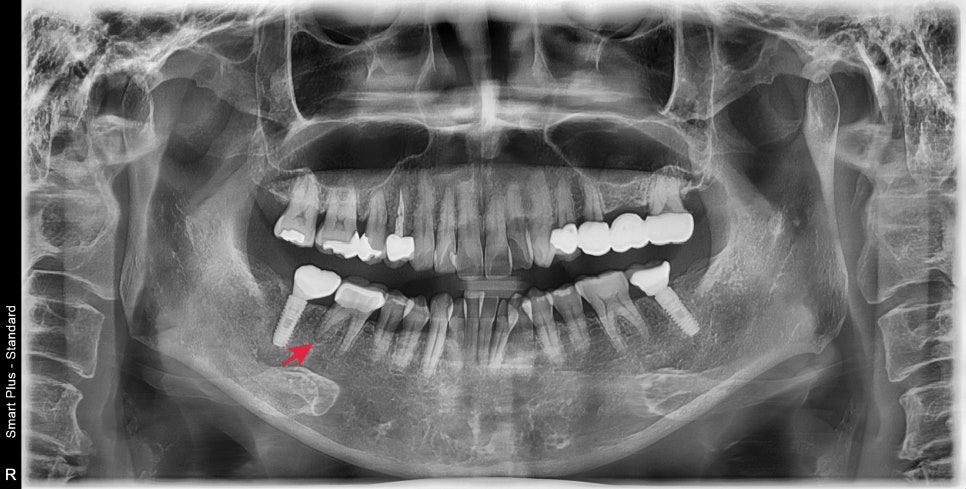

큰 엑스레이상에서 확인할 때 과거에 크라운치료를 받은 치아의 뿌리 주변이 염증소견이 보였습니다.

자세하게 확인하기 위해 해당 치아만 따로 엑스레이 촬영을 했습니다

어금니 뿌리가 4개가 있는데 모두 뿌리 쪽의 염증이 확인되었습니다.

통증이 있던 이유는 염증이 생기면서 압력이 생겨 불편감을 호소하시는 중이었습니다.

과거에 신경치료를 하시고 크라운을 씌운 상태에서 통증을 느끼셔서 내원해 주셨습니다

엑스레이상에서 뿌리 하방으로 염증소견이 보였습니다.

근관치료를 받으신지 오래되셨고 뿌리 쪽에 기둥도 심어져있어서

재근관치료가 어려워 보였습니다.